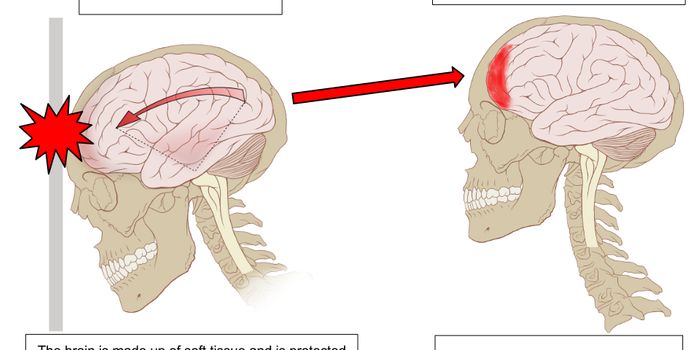

JUN 07, 2016NeuroscienceA traumatic brain injuries, or TBI, can be devastating and have long-lasting effects. In children these injuries can be ...

MAY 12, 2016NeuroscienceTraumatic brain injuries, or TBI, are known to cause a variety of problems. TBI has been indicated in Chronic Traumatic ...

MAR 23, 2016NeuroscienceWhile the subject of brain injuries, concussion and Chronic Traumatic Encephalopathy (CTE) have swirled around the NFL f ...

DEC 20, 2015Health & MedicineChildren commonly get concussions. Usually, those concussions happen while playing a sport. Concussions are caused by a ...